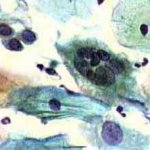

Δυσπλασίες τραχήλου μήτρας σοβαρού βαθμού (CIN III)

Ασυμπτωματική ασθενής 39 ετών. PH κόλπου 4,4. Κολποσκόπιση:

Στην δοκιμασία οξικού οξέως και στην δοκιμασία Lugol, αρνητική περιοχή, τόσο στο πρόσθιο, όσο και στο οπίσθιο χείλος του τραχήλου, σε ακτίνα 3-4 χιλ. και πλάτος περίπου 5 χιλ., με εικόνα διακριτικού επίπεδου μωσαϊκού.